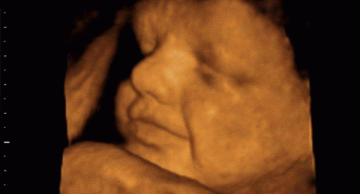

8 dị tật bẩm sinh thường gặp ở thai nhi mẹ bầu nên chú ý

Theo thống kê năm 2017 tại Việt Nam, ước tính cứ 33 bé ra đời lại có 1 bé mắc dị tật bẩm sinh. Bài viết này phân tích 8 dị tật bẩm sinh thường gặp nhất tại các bệnh viện phụ sản theo báo cáo thường niên, đồng thời đưa ra giải pháp giúp mẹ bầu có được thai kỳ khỏe mạnh nhất!

Dấu hiệu thai nhi bị dị tật mẹ bầu nhất định phải biết

Là cha mẹ ai cũng mong muốn con mình sinh ra lành lặn và mạnh khoẻ. Thế nhưng trường hợp con sinh ra bị dị tật vẫn chiếm một tỷ lệ nhất định. Vậy nên, nhận biết dấu hiệu thai nhi dị tật là điều đa số các bậc cha mẹ quan tâm.